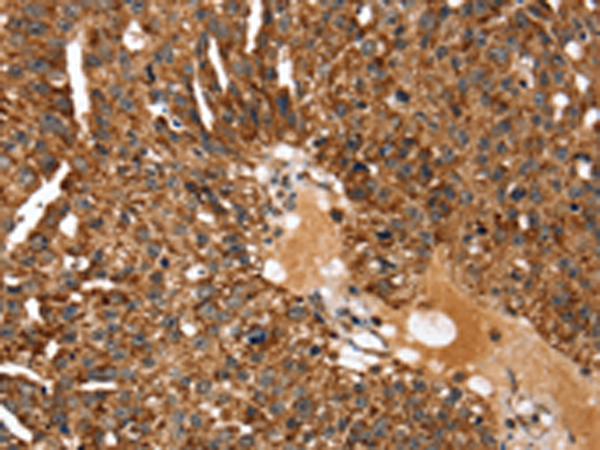

IHC positive control:

Human breast cancer